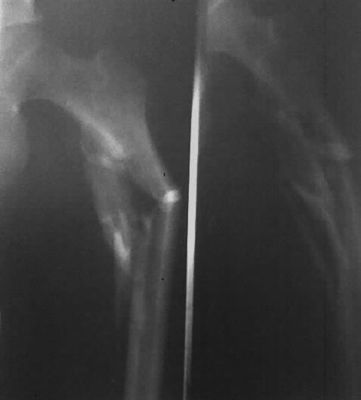

Фильм медицинского рентгеновского снимка Конида сухой (КНД-А/Ф) имеет слой изображения и защищает слой на различной стороне сизоватых оснований полиэстера, и никакой чувствительный серебряный галоид в обоих слоях. Фильм приспособлен для термального принтера для печати цифрового изображения которое обработано и сохранено в компьютере, достигнуть увеличенного качества изображения рентгеновского снимка. Сравненный к традиционному серебряному галоиду обрабатывая, процедура более удобна и скорость обработки более быстра. Между тем, она достигает к цели защиты среды потому что вся процедура свободна химикатов.